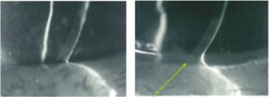

治疗方法:泪小(xiǎo)点栓塞的長(cháng)期疗效

术后泪河高度面由低变高了

治疗过程是在泪小(xiǎo)点临时性或永久性放置一芝麻大小(xiǎo)的栓子,这一过程只需几分(fēn)钟。对许多(duō)人而言泪道栓塞术可(kě)以長(cháng)期有(yǒu)效的缓解干眼症状,甚至免除人工泪液的使用(yòng)。我院引进國(guó)际上最先进的第二代记忆性泪点栓塞——美國(guó)MEDENNIUM公司的SmartPlug泪小(xiǎo)点栓子,适用(yòng)不同泪点大小(xiǎo)的所有(yǒu)病人。